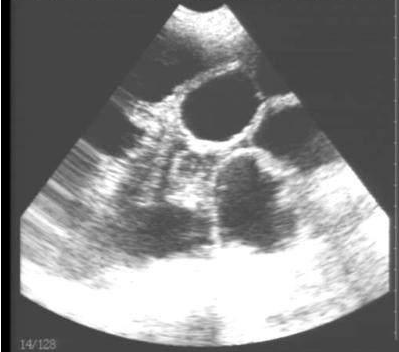

豬用B超機(jī)檢測(cè)有胎兒圖像

需要注意的是,出現(xiàn)云團(tuán)狀必須雙側(cè)檢查加以確認(rèn).根據(jù)B超機(jī)顯示圖我們大致可以判斷孕齡.圖像呈橢圓或者卵圓形大致為30天左右孕齡;圖像呈橢圓形或者卵圓形外,有明顯發(fā)亮骨骼圖像大致為50孕齡左右;圖像囊胚消失,發(fā)亮處隱約可見(jiàn)竹節(jié)狀東西為成型胎兒骨骼,一般為后期80孕齡以后。一般B超機(jī)成像會(huì)出現(xiàn)三種顏色,白色、黑色、灰色。白色為密度較高的物體,如骨骼或者結(jié)實(shí).黑色一般為液體,包括血液、羊水、組織間隙液體、炎癥病灶等?;疑话銥閷?shí)質(zhì)性物質(zhì),如肌肉。